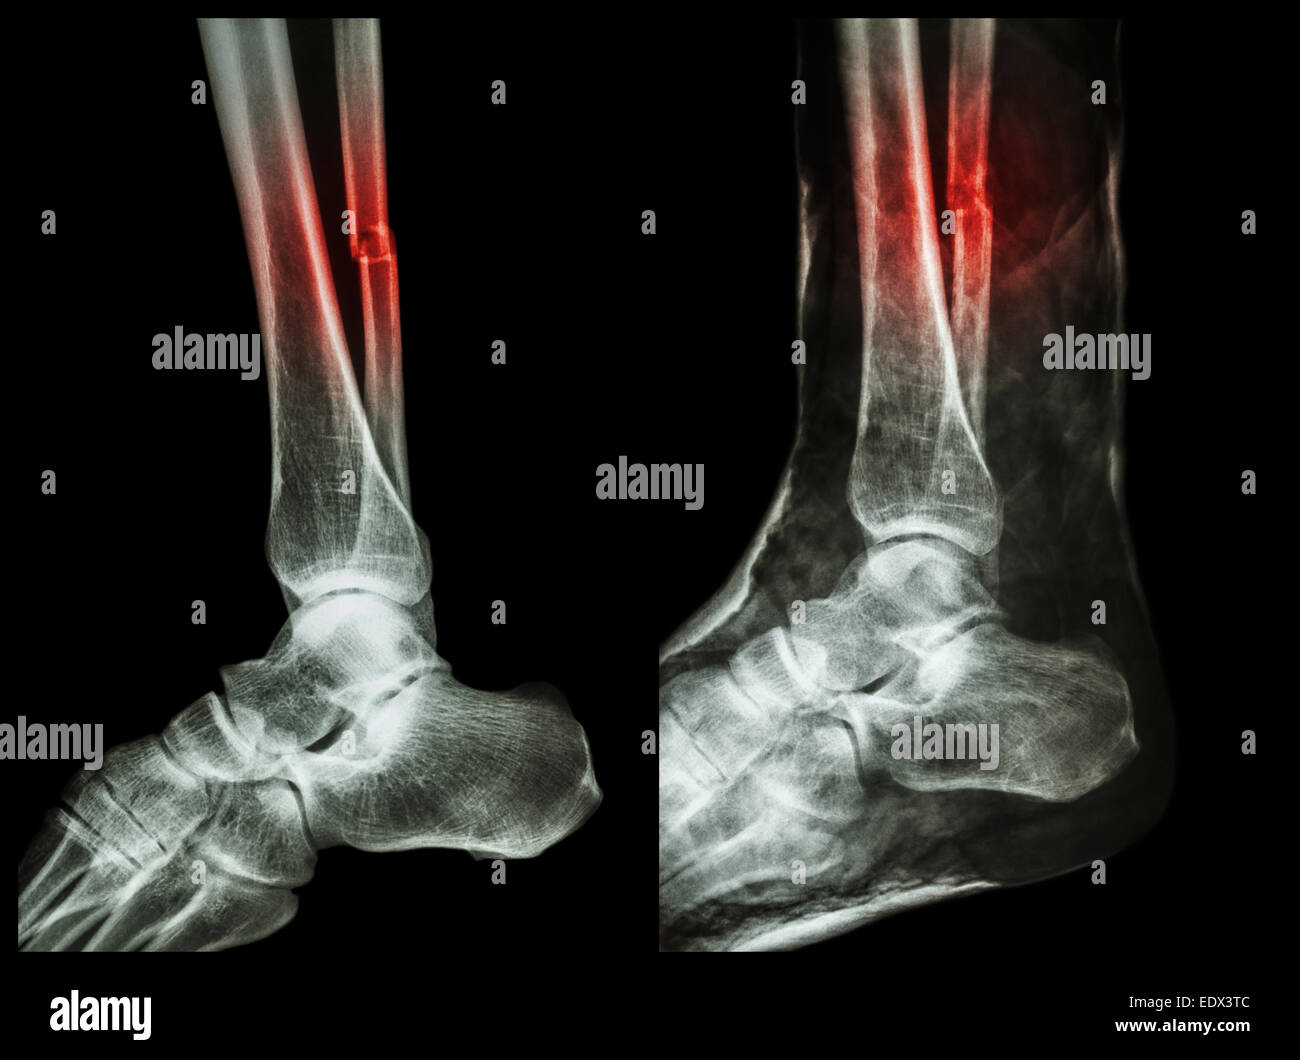

Diagnostic Methods and Grading

A medical professional will usually perform a physical examination, specifically the “Squeeze Test” or the “External Rotation Stress Test,” to confirm a diagnosis. In many cases, X-rays or an MRI may be required to rule out fractures of the fibula or to determine the severity of the ligament tear.